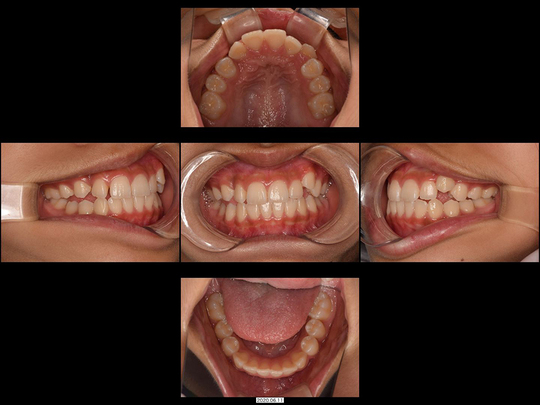

Mさん 20代 男性

矯正前

画像をクリックで拡大

矯正後

治療の説明

マウスピース型矯正装置を使った矯正治療にて、下あごのみ治療しました。歯は抜いておりません。

治療の期間・回数

10か月、8回

​費用

563,200円